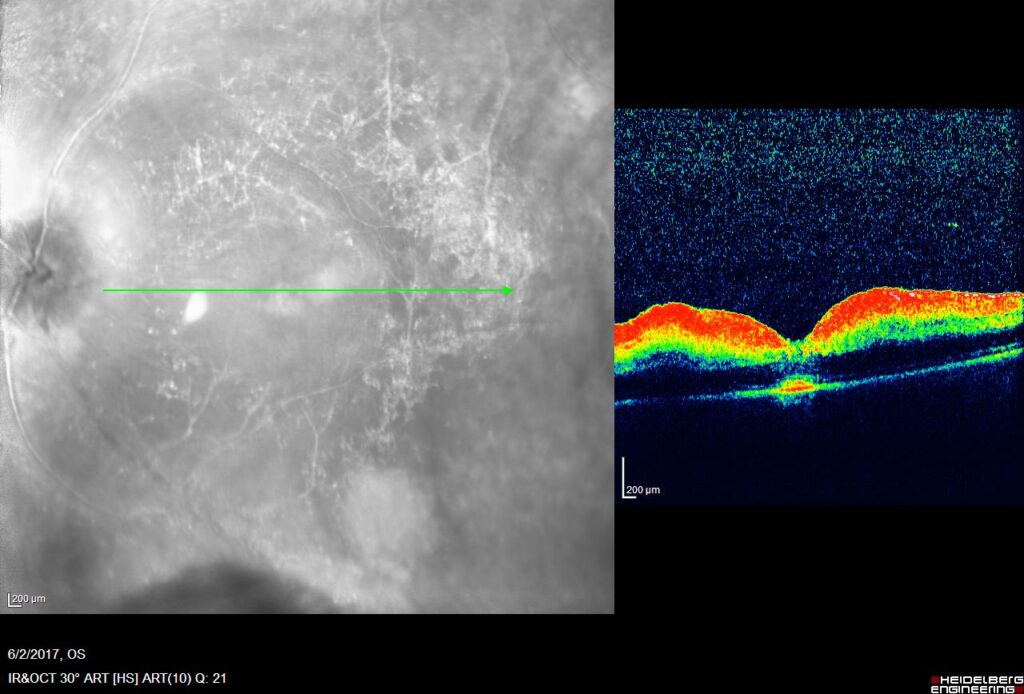

There is no standard number. Treatment is individualized. We usually start with monthly doses and check the result with an OCT (optical coherence tomography) scan. If the swelling subsides, the injections are diluted or stopped.